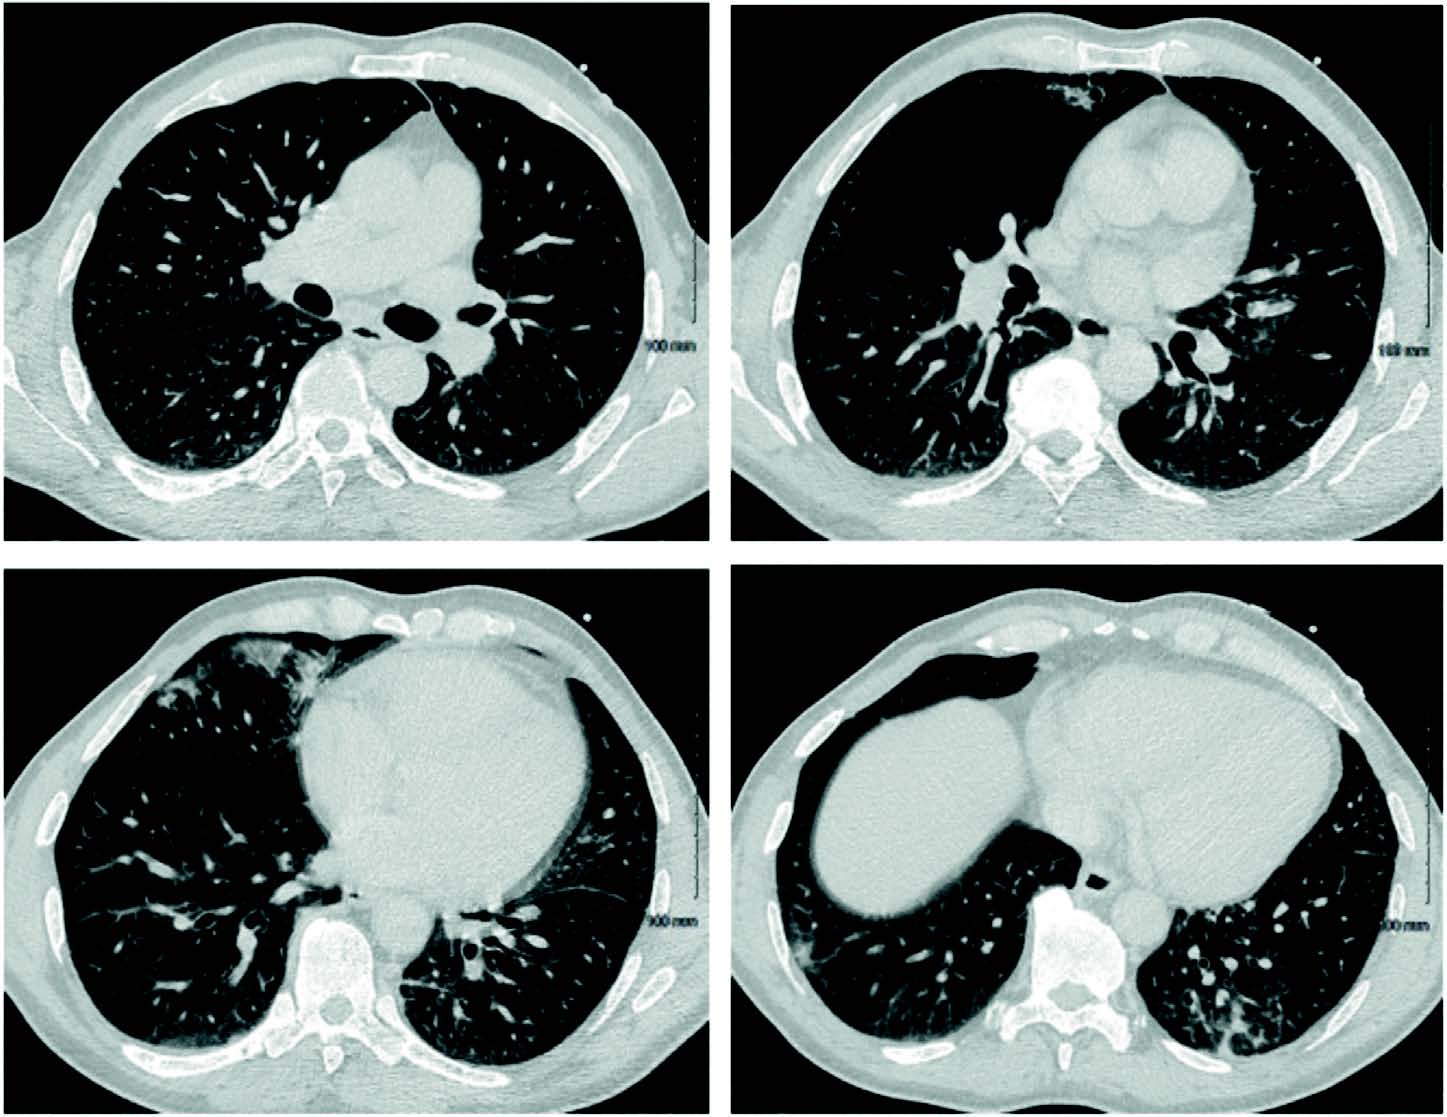

À J40, l'état respiratoire du patient continue de s'aggraver avec une majoration de l'oxygénoréquerance jusqu'à 12L ainsi que l'apparition de crachats hémoptoïques motivant la réalisation d'un nouveau scanner thoracique (figure 2) révélant l'apparition d'une condensation circulaire avec du verre dépoli en son centre au niveau du lobe inférieur gauche décrivant le signe du halo inversé ou signe de l'atoll 1.

Figure 2. Coupes transversales du scanner thoracique à J40.

Le signe du halo inversé se caractérise par la présence d'une opacité en verre dépoli au centre, entourée par une condensation périphérique. Ce signe doit amener à envisager plusieurs diagnostics possibles selon le statut immunitaire : pneumonie organisée, granulomatose avec polyangéite ou infarctus pulmonaire si immunocompétent, une mycose pulmonaire invasive si immunodépression (3-5).

Dans notre cas, les prélèvements endoscopiques sont impossible du fait de la mécanique respiratoire défaillante, mais le diagnostic d'infection fongique invasive probable est posé devant le terrain à risque, le scanner très évocateur et confirmé par la positivité de la PCR mucorale sanguine.